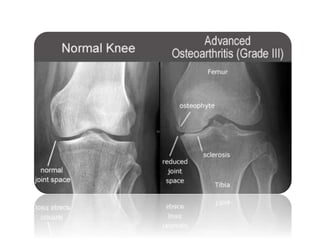

Radiology:

x-ray

-Anteroposterior the patient standing and bearing weight

-Findings :

- The tibio-femoral joint space is diminished

(often only in one compartment)

- subchondral sclerosis.

- Osteophytes and subchondral cysts

- sometimes there is soft-tissue calcification in the

suprapatellar region or in the joint itself

(chondrocalcinosis).